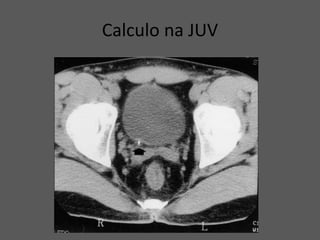

Calculo na JUV